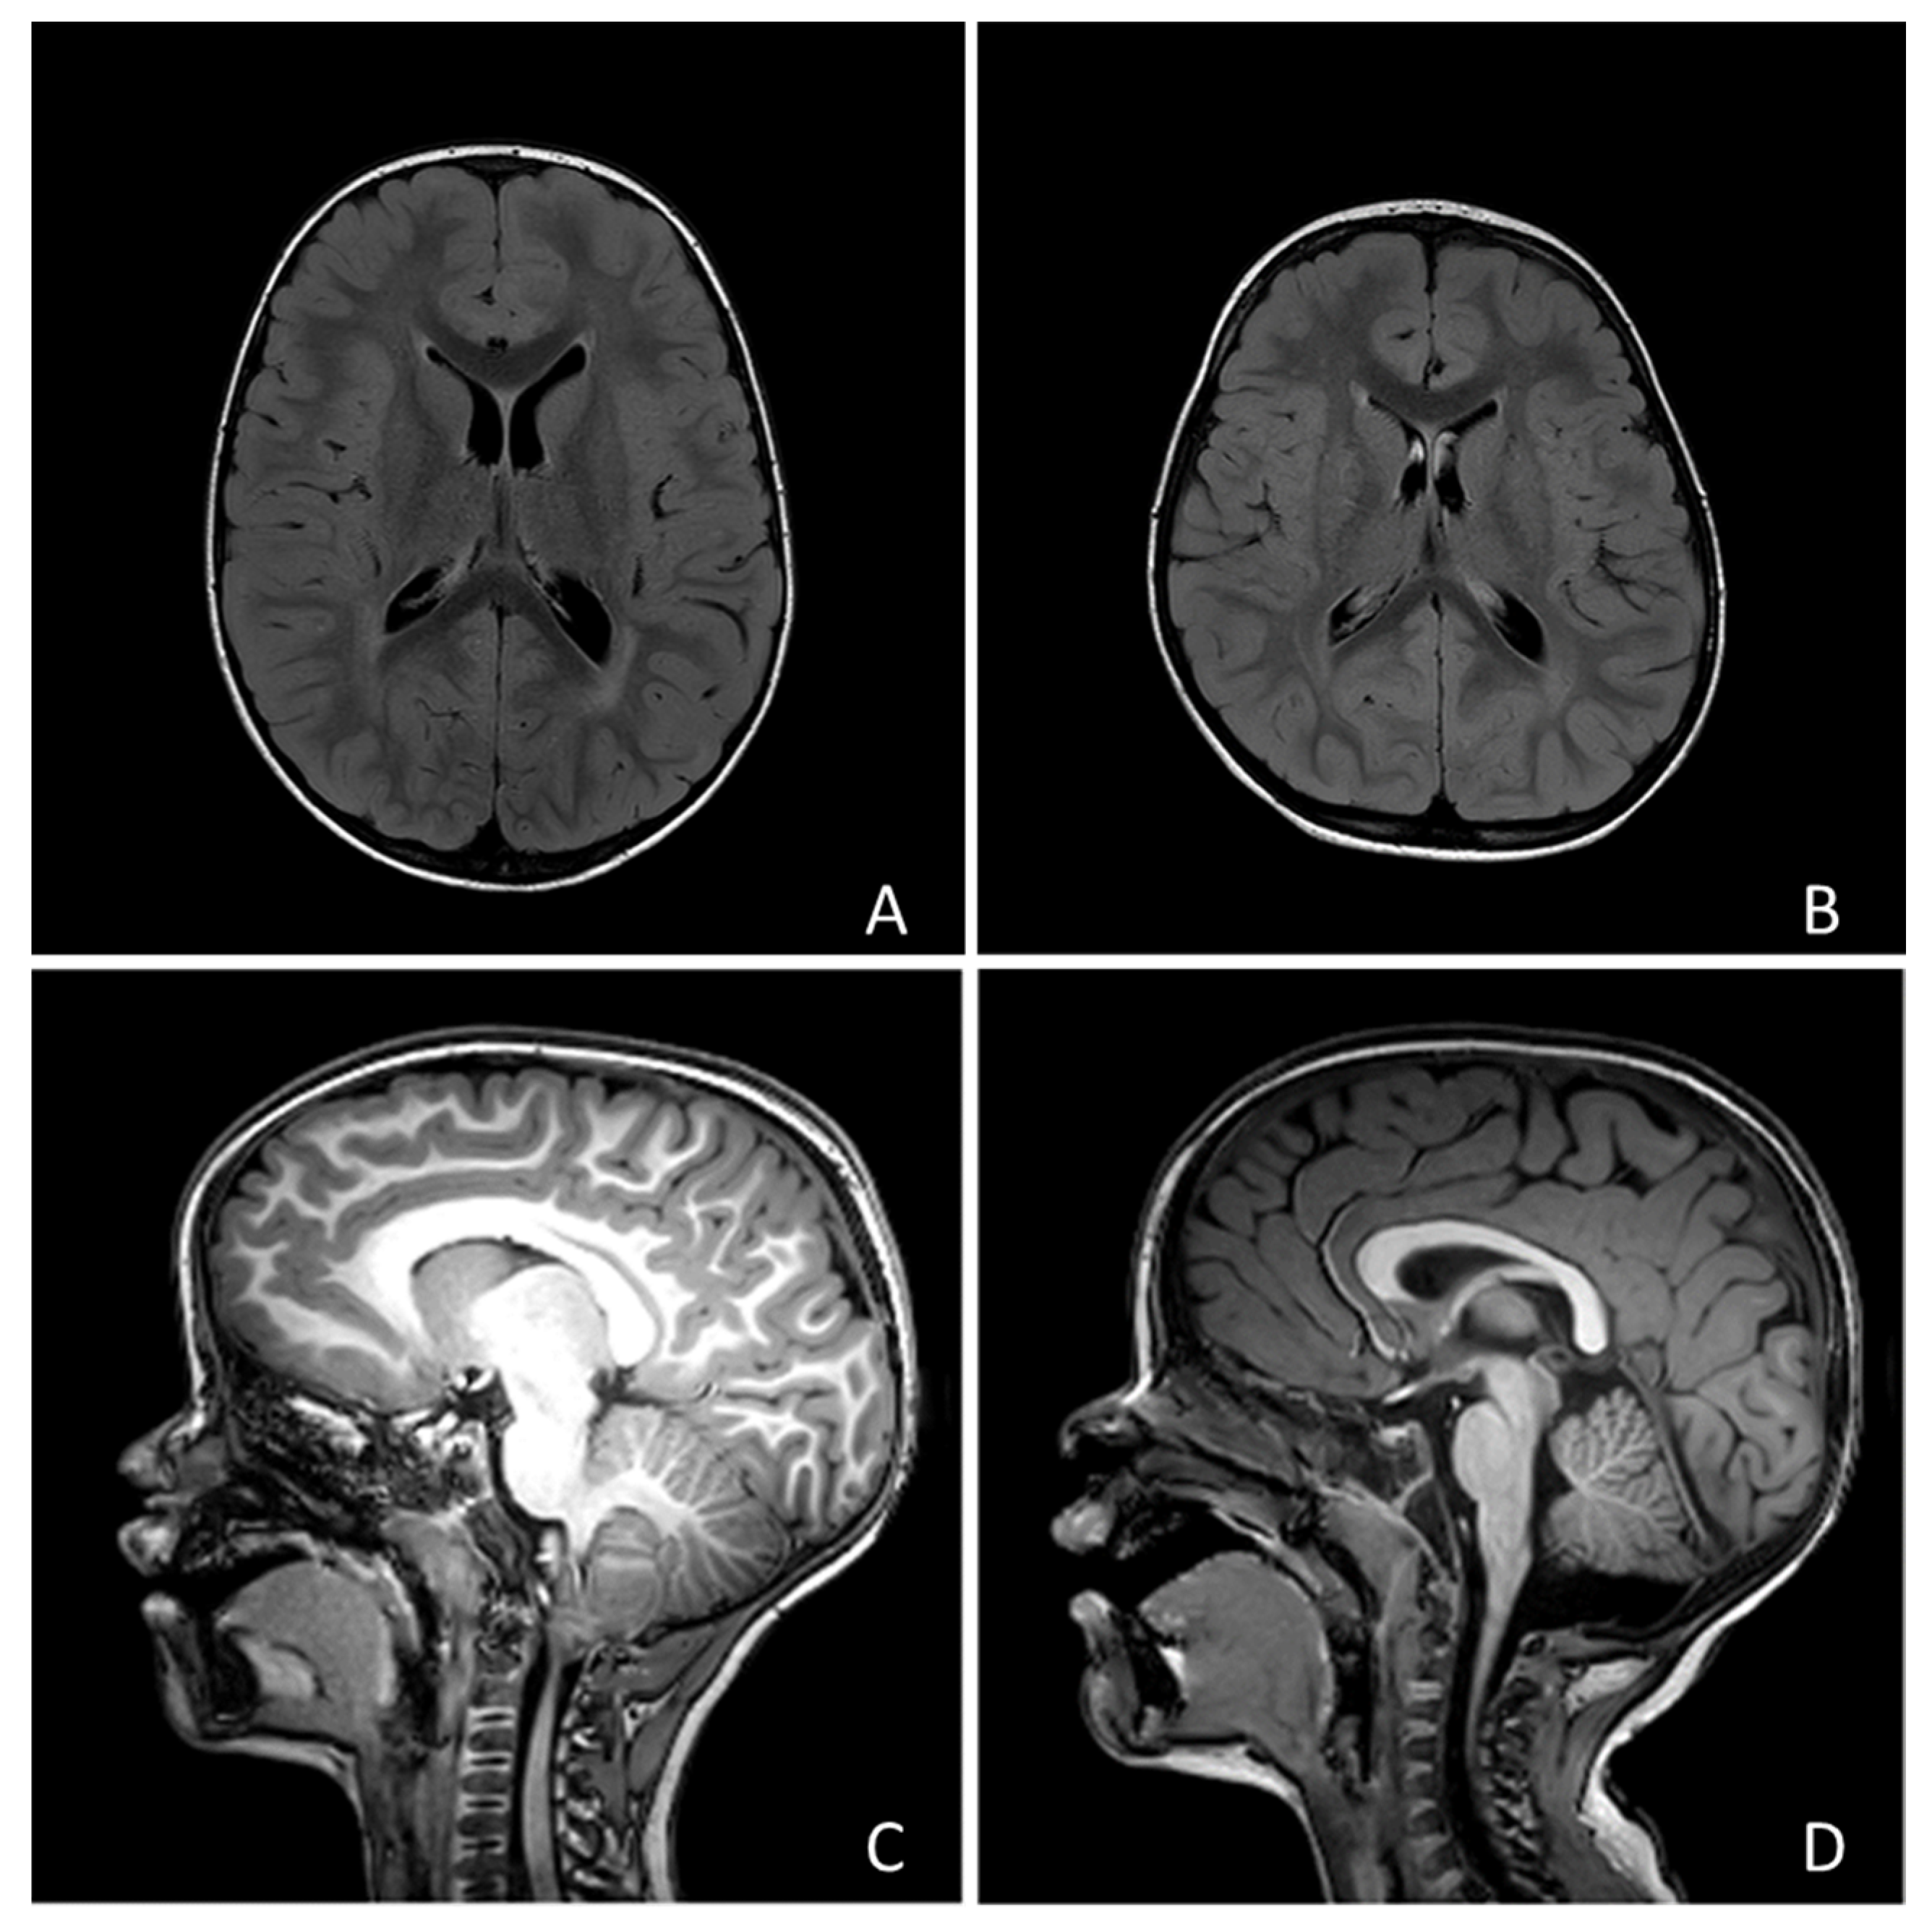

No child showed focal neurological signs, but 190 children (69.5%) presented with developmental delay. Only 1 individual (0.35%) received a diagnosis of epilepsy (focal epilepsy of unknown etiology). Twenty-four subjects underwent MRI and abnormal findings were found in 15 cases (examples in Figure 1). Among these cases, 7 showed posterior fossa abnormalities (1 vermian hypoplasia, 2 Arnold-Chiari type 1 malformation, 1 mild fourth ventricle enlargement, 3 mild cisterna magna enlargement), 3 had a ventricular asymmetry, 2 a slight enlargement of the perivascular spaces, 1 focal heterotopia, 1 mild white matter signal abnormalities, 1 mild white matter signal and macrocephaly.

Figure 1.

Four examples of the neuroradiological findings we reported in the text: (A) Macrocephaly and hyperintensity of peritrigonal white matter; (B) Mild asymmetry of lateral ventricles; (C) Chiari type I malformation; (D) Slight enlargement of Cisterna Magna.